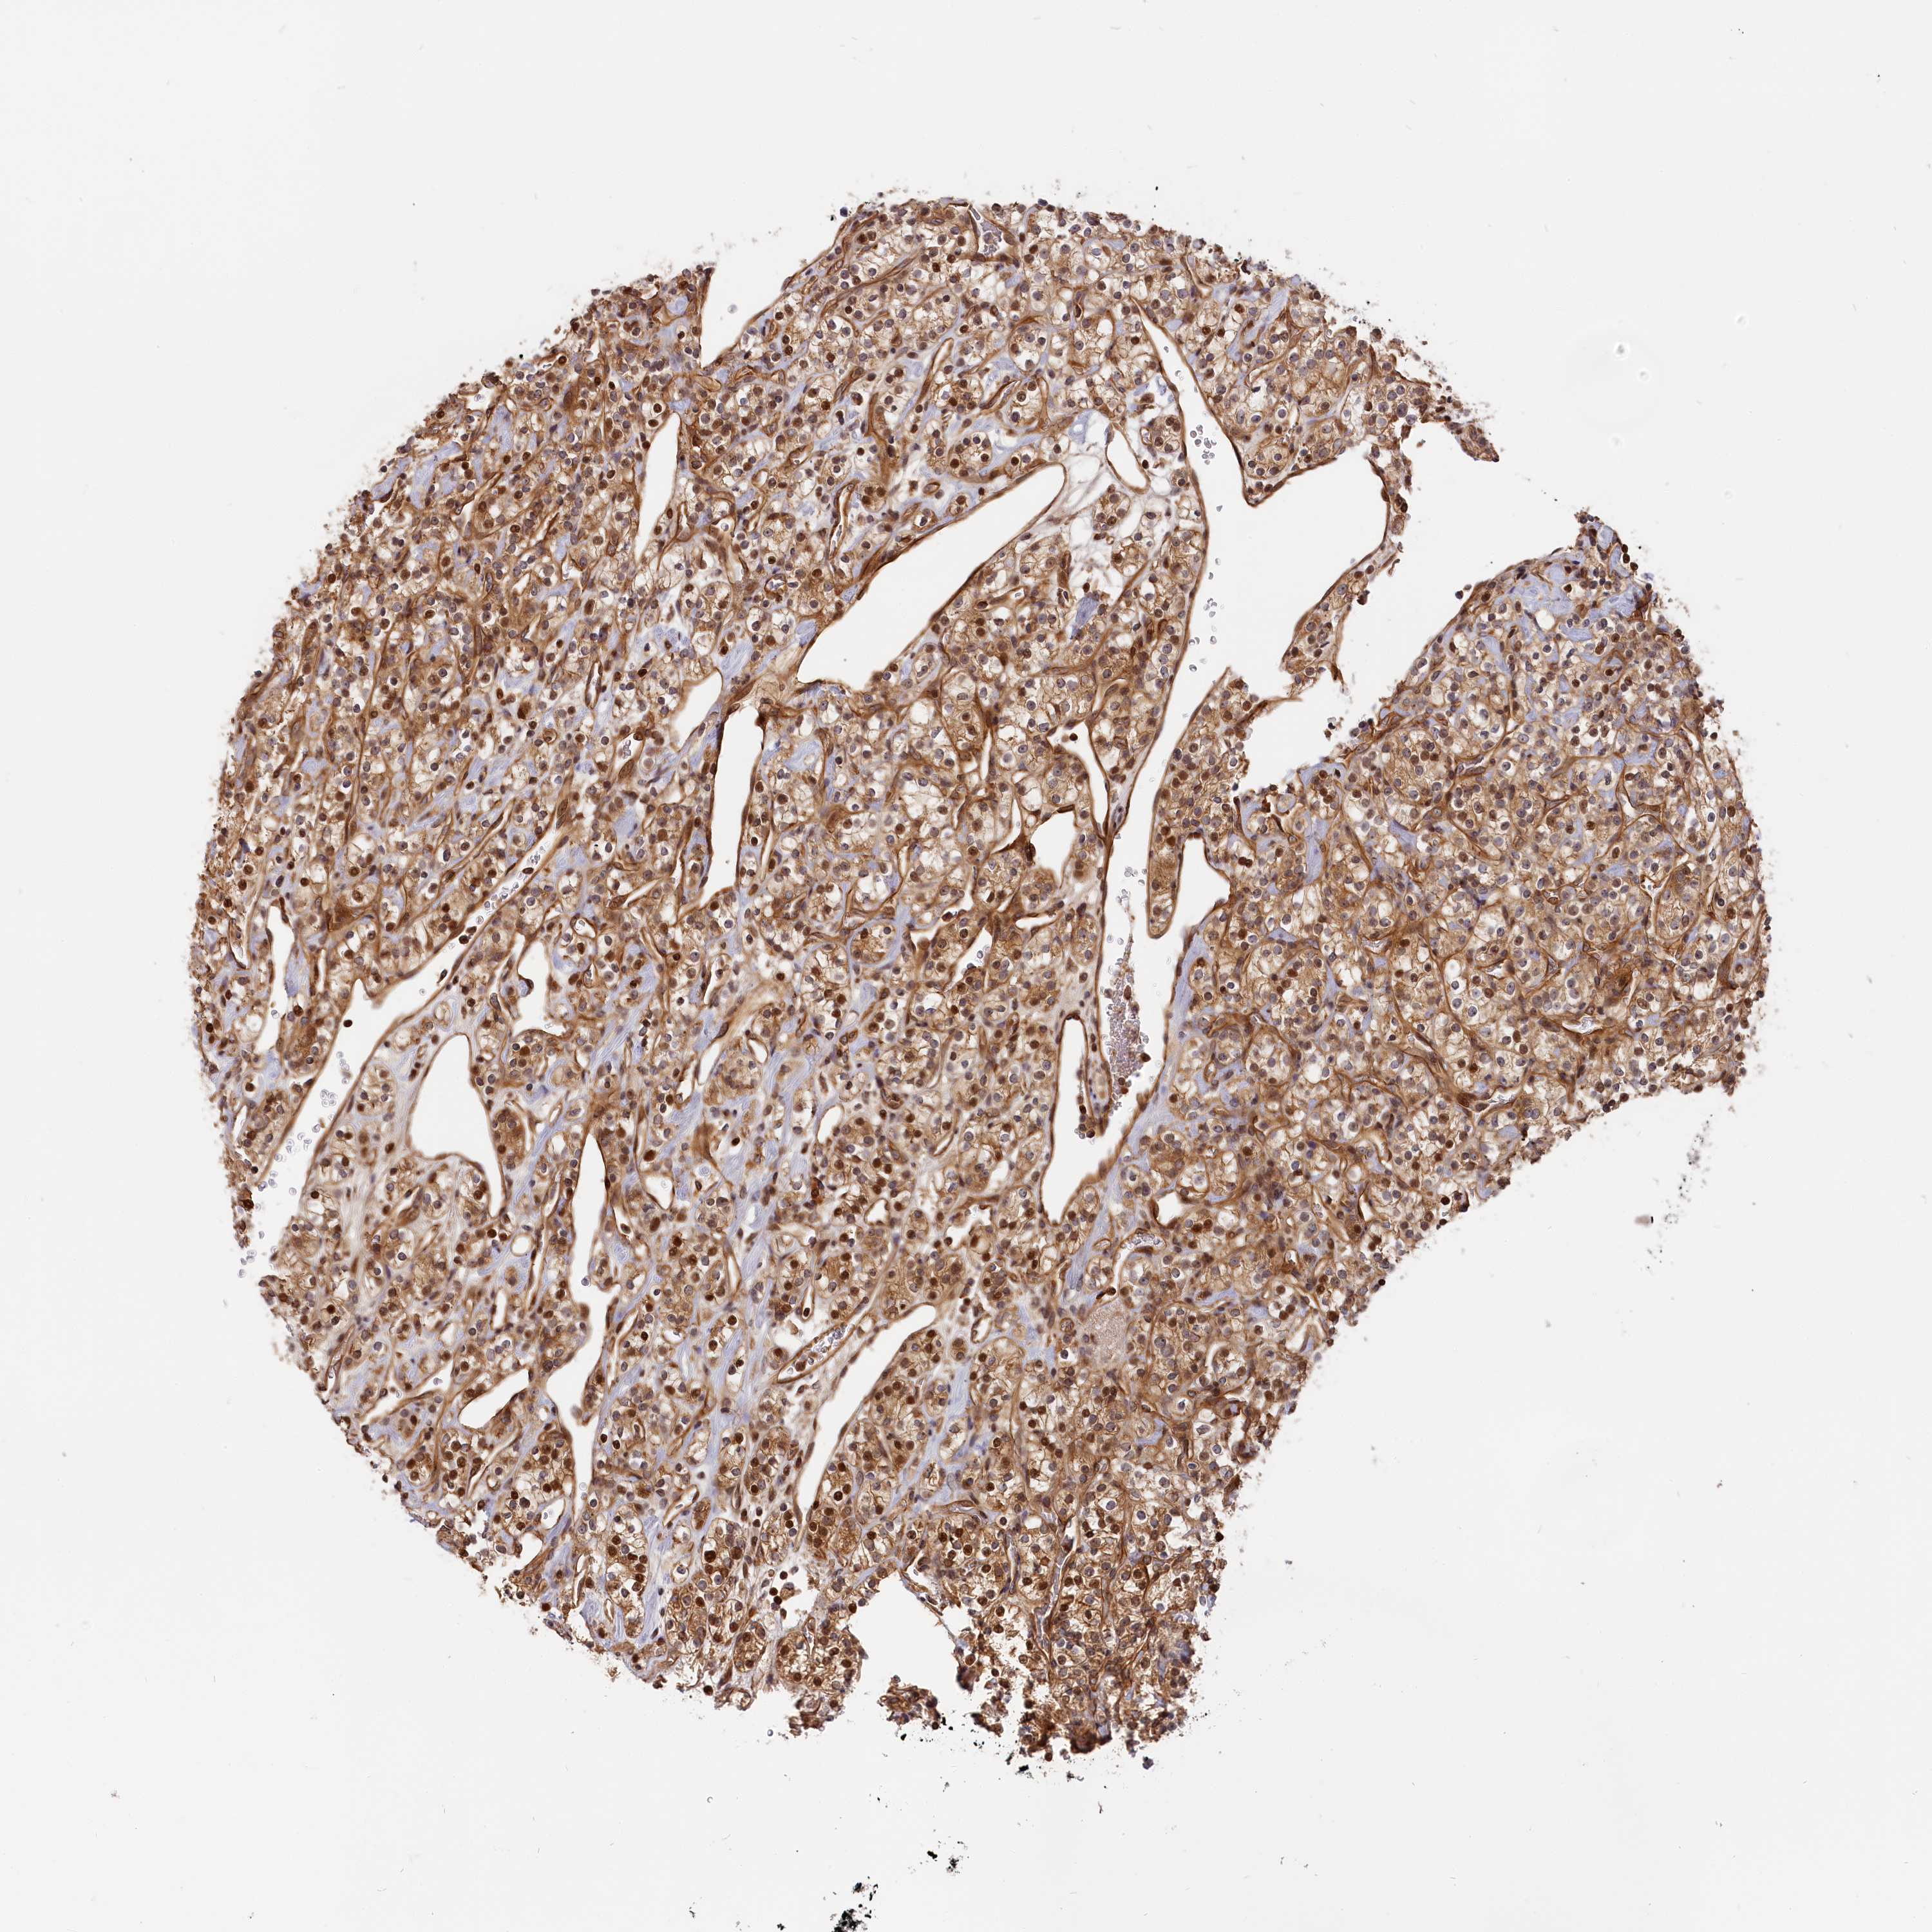

CANCER RENAL CANCER Show tissue menu

KICH TCGA KIRC TCGA KIRC VALIDATION KIRP TCGA PROTEIN RCC CPTAC PROTEIN EXPRESSION